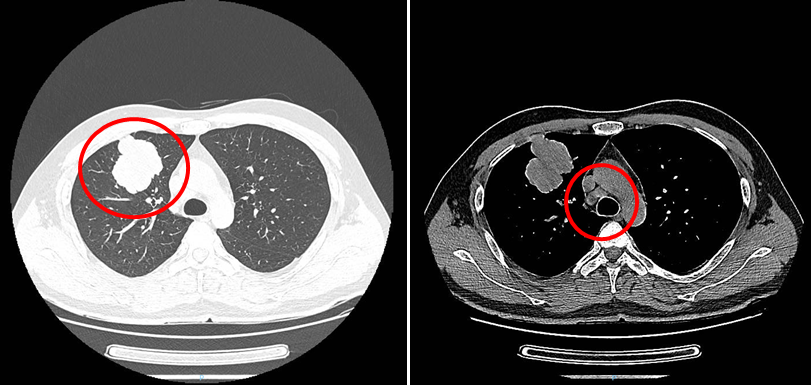

疗效评估(2021-2-23):两周期后,胸部CT、PET/CT提示肿物及淋巴结缩小,SUV值降低;ctDNA阴性。疗效评估提示疾病PR,靶向治疗有效,预期可完全切除。

胸部CT提示肿物及淋巴结缩小

PET/CT提示肿物及淋巴结糖代谢摄取均降低